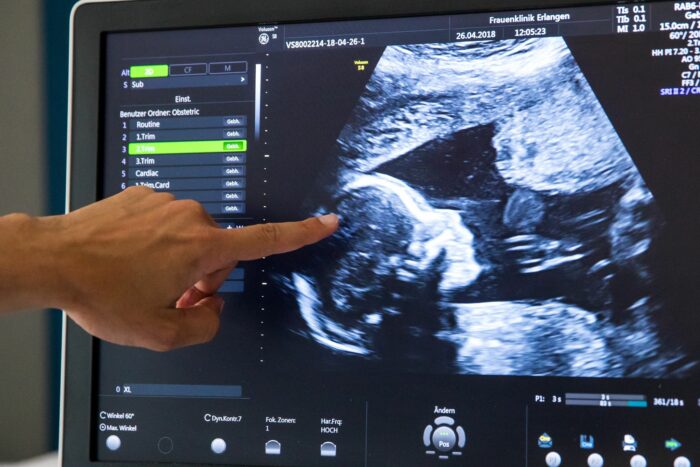

Seit einigen Jahren streiten Forscher darüber, wann unser Körper von Viren, Bakterien und anderen Mikroorganismen besiedelt wird. Während lange Zeit galt, dass dies erst im Verlauf der Geburt erfolgt, berichteten jüngere Studien, dass schon Fruchtwasser- und Plazentaproben solche Mikroorganismen enthielten. Das würde nahelegen, dass bereits Föten ein sogenanntes Mikrobiom haben. Ein internationales Team widerspricht dem nun deutlich: Aufgrund einer multidisziplinären Analyse, die im Fachblatt «Nature» veröffentlicht wurde, stellte es fest, dass der Mutterleib gewöhnlich doch steril ist.

Lange Zeit galt, dass das ungeborene Kind, sowie die Gebärmutter, in der es heranwächst, einschließlich der Plazenta (Mutterkuchen) und des Fruchtwassers bei einer gesunden Schwangerschaft steril sind. Seit 2010 berichteten jedoch mehrere Forschungsteams, Bakterien in Proben der Plazenta und des Fruchtwassers gefunden zu haben, und schlossen daraus auf das Vorhandensein eines fötalen Mikrobioms, was bedeuten würde, dass die gängige Vorstellung über die Entwicklung des Immunsystems beim Ungeborenen völlig neu bewertet werden müsste.